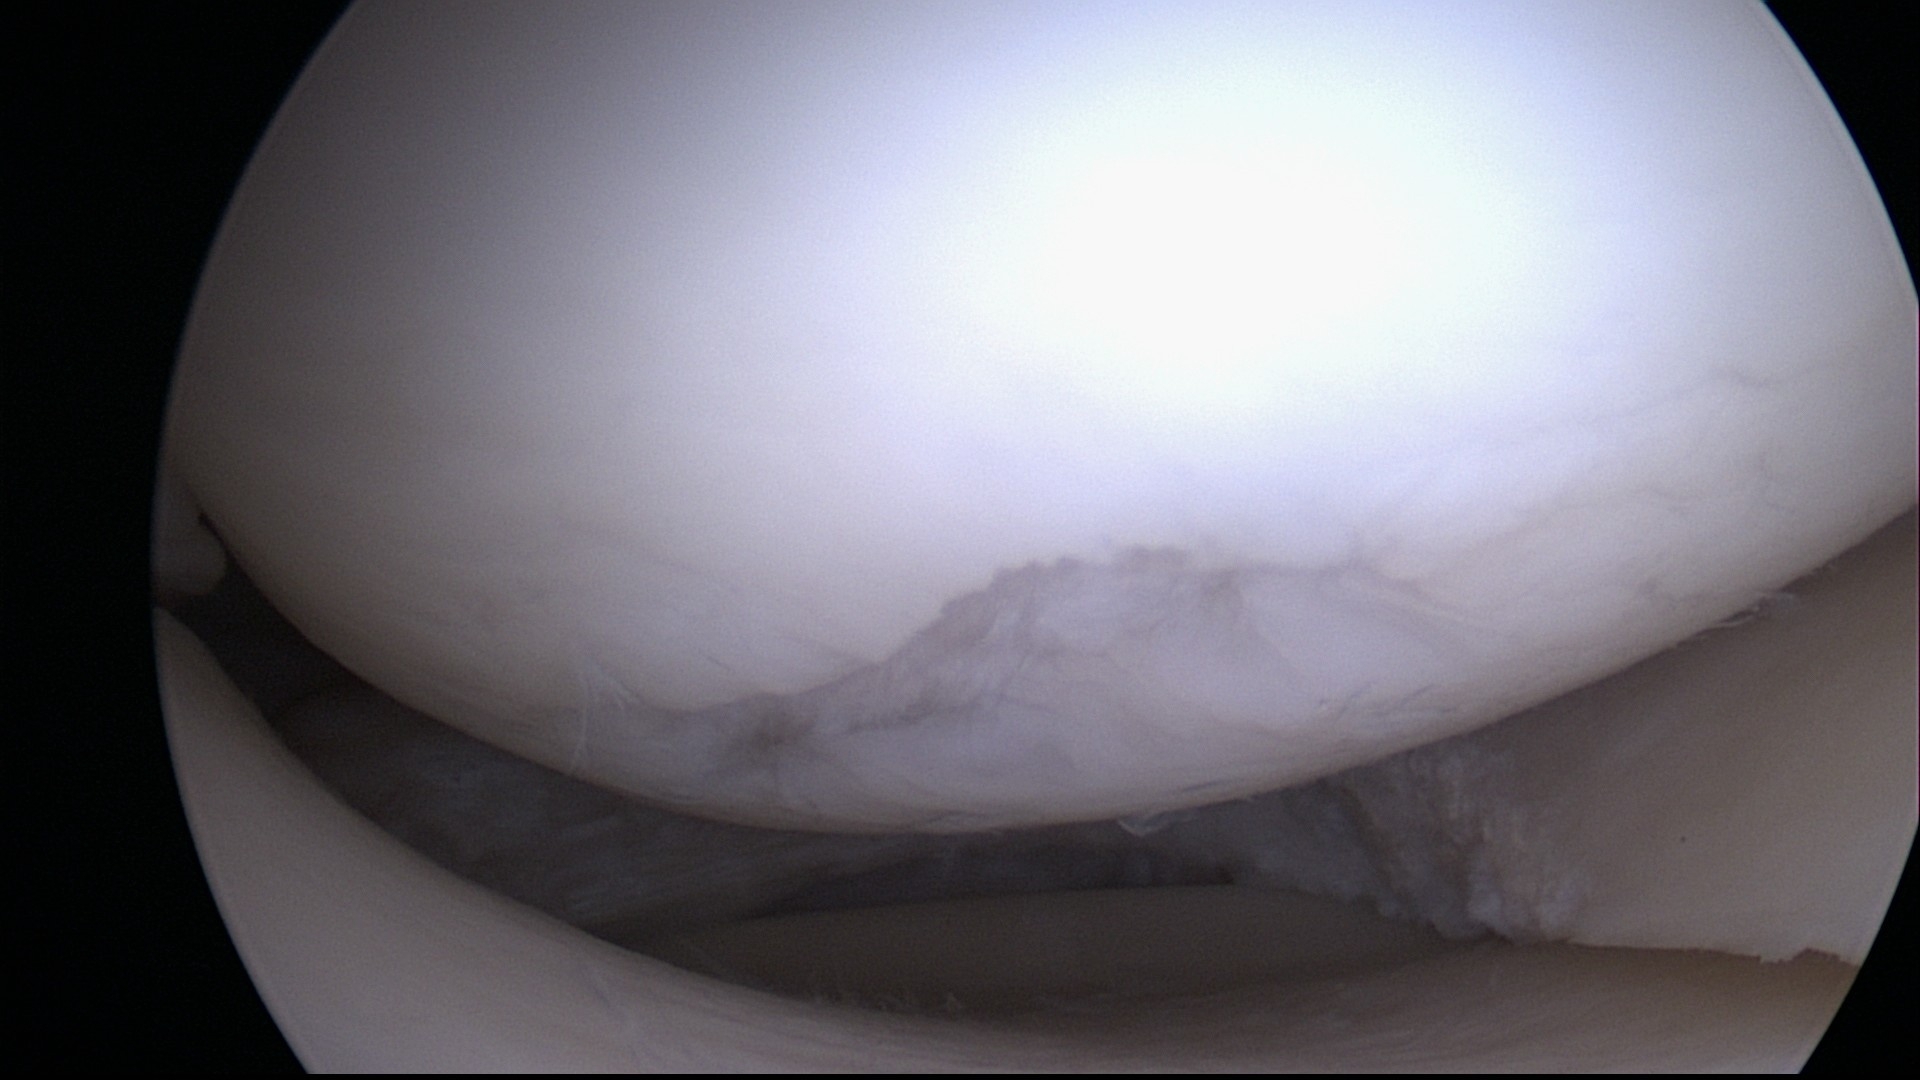

Es gibt fünf Grade der Knorpelschädigung nach Kellgren und Lawrence (Grad 0 bis Grad 4), wobei der Grad der Schädigung nicht direkt die notwendige Therapie vorgibt. Einen ebenso großen Einfluß auf die Therapie hat der Ort der Schädigung, da ein geringer Schaden (Grad 0 bis 2) in einer Hauptbelastungszone (beispielsweise am Knie) große Probleme bei Sport und Belastung verursachen kann, während ein tiefgreifender Schaden des Knorpels an einem Ort ohne Belastung (etwa dem Ellbogengelenk des nicht führenden Armes) sogar unbemerkt bleiben kann.

Abb. 1: 1.-gradiger Knorpelschaden im Knie bei Meniskusriss

Abb.2: 3.gradiger Knorpelschaden am Knie nach Meniskusteilentferung